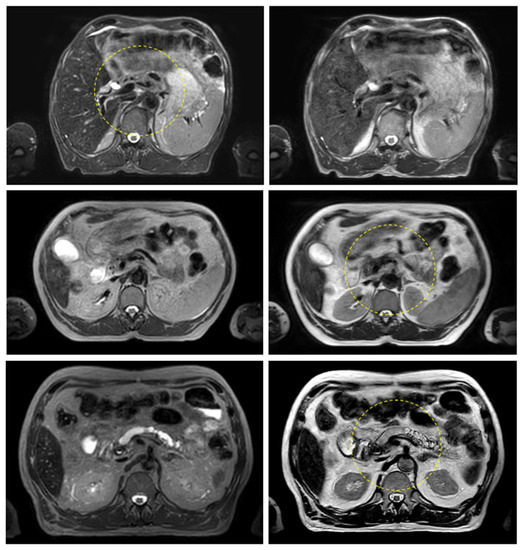

Figure 3 and Figure 4 show the comparison between the T2w-Nav and T2w-Ave sequences acquired during the Unity-MR simulation sessions for several liver and pancreas cases, respectively. T2w-Nav required on average 5–6 min to acquire a full image series depending on each patient’s breathing pattern. In contrast, the T2w-Ave acquisition time was fixed to roughly 4 min. In certain instances, the T2w-Ave scan time was increased by 1–2 min to provide extended superior–inferior coverage. In particular, Figure 3a shows the two liver targets bundled together while Figure 3b depicts two out of four targets present in the same imaging plane. The post-operative targeted areas with RT for three pancreas cases are shown in Figure 4.

The quality of the target and OARs visualization varied per patient depending on motion characteristics. Figure 3 highlights the advantage of using T2w-Nav over the T2w-Ave for the liver cases. The T2-Nav performed best when motion was more than 5–6 mm. The signal collection was efficient and robust even when patient breathing under compression exhibited an irregular pattern. However, T2-Nav acquisition became impractical when there was little breathing motion as the triggering algorithm was not able to efficiently collect data in the exhale phase (long scanning time). Due to a slightly different T2w contrast and robust data acquisition under low organ motion amplitude, the T2-Ave scan was used as the main imaging method for pancreas. This is highlighted in Figure 4. T2-Ave became less efficient when large organ excursions were present as they introduced significant amounts of blur, which prevented the definition of both the target and OARs.

Figure 3. Liver examples depicting the comparison between the T2w-Nav (first column) and T2w-Ave (second column) image sequences. The target(s) location is identified by the yellow arrow. The samples correspond to Patients 7, 8, and 9 as per Table 1. These cases were planned with the T2w-Nav image data.